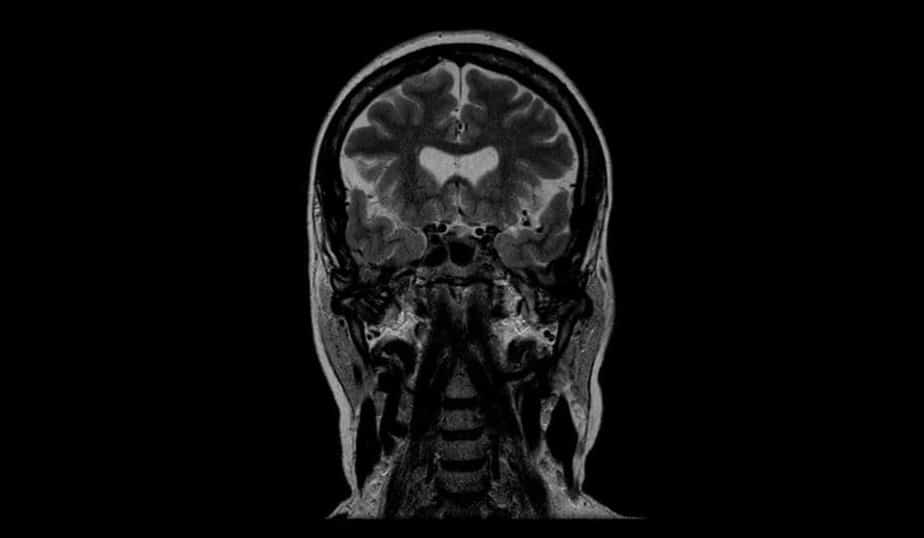

Manyetik rezonans görüntüleme (MRG) ise doğrudan kemik yapısını değil, kemik iliği ve çevre dokuları inceler. Ancak belirli iskelet hastalıklarının teşhisinde MRG tamamlayıcıdır. Bu yazıda tomografinin önemi ve detayları ağırlıklı olarak BT tekniği üzerinden anlatıldığında, aldığım hasta deneyimlerinden yola çıkarak gerçek uygulama bilgilerini de paylaşacağım.